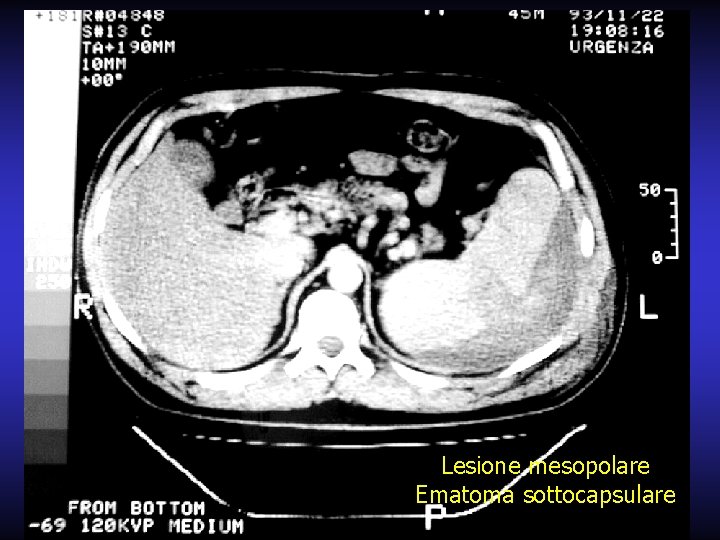

Lesione mesopolare Ematoma sottocapsulare